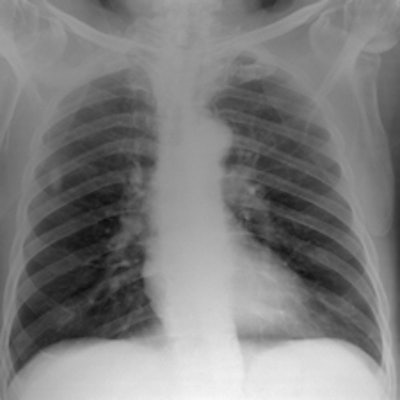

Simulated chest images of an average-sized patient reconstructed at 50 kVp (a) and 150 kVp (b). Image (a) is of higher contrast, which is expected. All images courtesy of Craig Moore.For average-sized patients, image quality improved when tube potential was reduced compared with the reference (102 kVp) and no scatter rejection was indicated. For obese patients, it has been shown that an antiscatter grid is indicated and should be used in conjunction with as low a tube potential as possible (while allowing exposure times, 20 msec), the researchers wrote. It is also possible to reduce receptor air kerma by 50% without adversely influencing image quality. They also found rib contrast did not interfere at any tube potential.

In 50 average patients who were reconstructed without scatter rejection, readers gave higher marks for images acquired with lower tube potential (kVp) settings, demonstrating that image quality improves with lower kVp, the researchers said. Visual grading analysis system scores ranged from 0.41 for 50 kVp to 0.03 for 109 kVp, but there was very little difference between image quality at tube potentials greater than 102 kVp (0.03 at 109 kVp to 0.07 at 150 kVp), according to the authors.